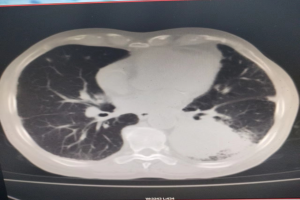

该患者罹患晚期肺癌,此次因发热伴呼吸急促入住区人民医院呼吸与危重症医学科。患者入院后,主要症状为呼吸急促,稍活动即感气喘,日常生活(穿衣、吃饭等)能力受限,胸部CT提示左肺下叶肿块,结合临床符合肺癌伴周围阻塞性炎症的特点,考虑肿瘤新生物堵塞管腔致呼吸急促,发热与阻塞性肺炎有关。经医生全身评估后,明确患者已无手术机会,其本人及家属均拒绝接受放化疗及免疫治疗。

术前胸部CT评估